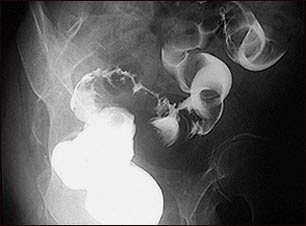

En esta placa nos muestra un cáncer de esófago.